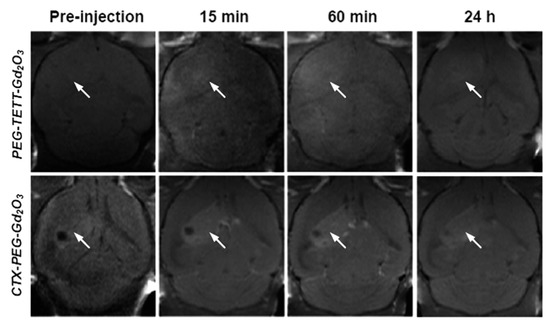

- Ahmad, M.Y.; Ahmad, M.W.; Cha, H.; Oh, I.-T.; Tegafaw, T.; Miao, X.; Ho, S.L.; Marasini, S.; Ghazanfari, A.; Yue, H.; et al. Cyclic RGD-Coated Ultrasmall Gd2O3 Nanoparticles as Tumor-Targeting Positive Magnetic Resonance Imaging Contrast Agents. Eur. J. Inorg. Chem. 2018, 2018, 3070–3079. [Google Scholar] [CrossRef]